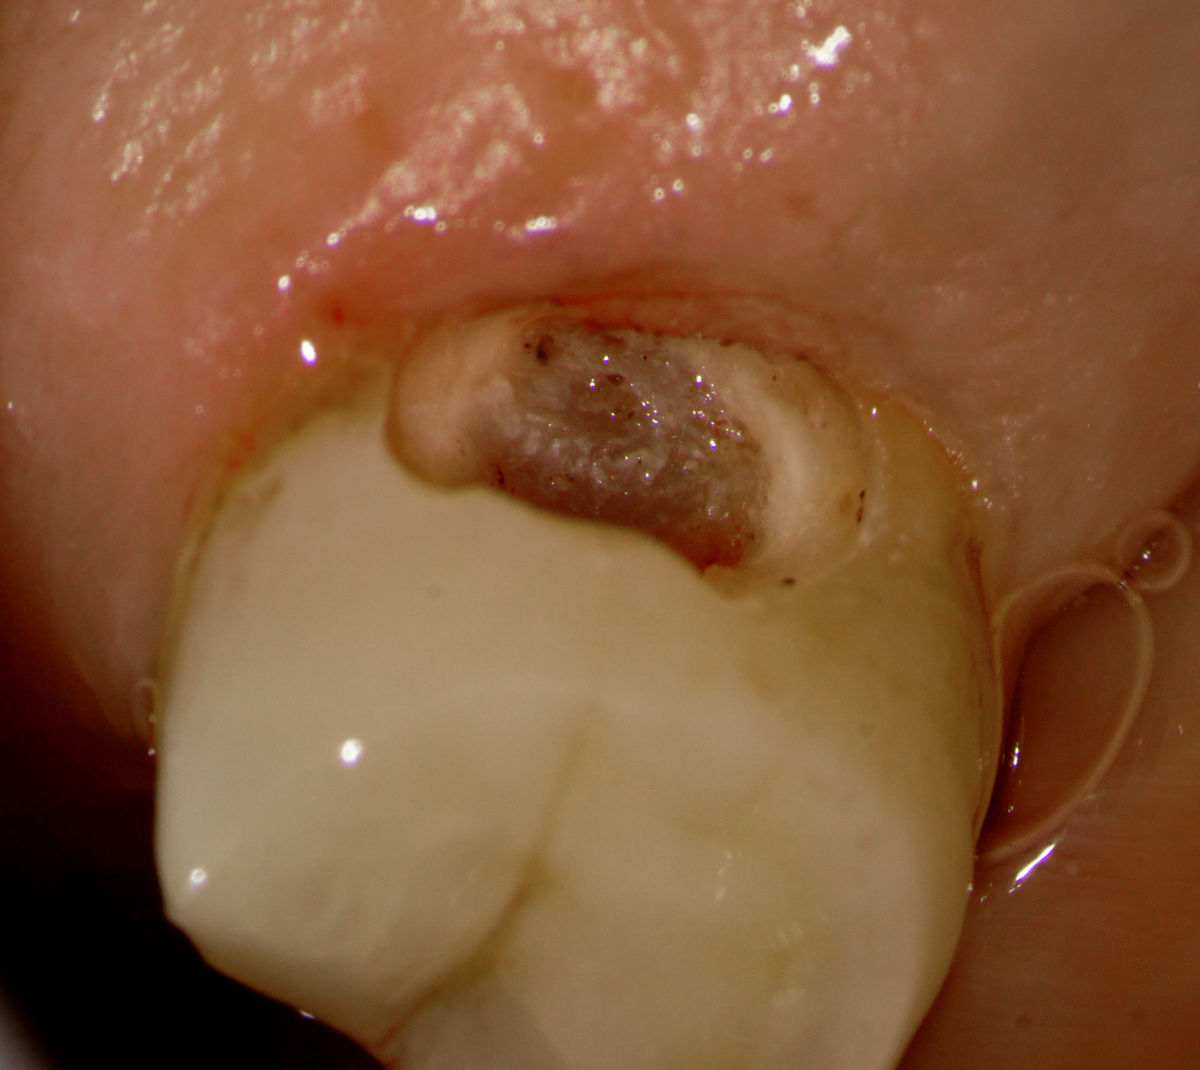

– Sub-gingival caries distal to an isolated #13

– Gingivectomy and isolation done

– Caries driven access through the distal (missing #12 and #14 made this approach possible)

– No post-endodontic restoration planned as the patient is a partial denture user (maxillary an mandibular) an I don’t think she will generate enough functional load for a structural failure.